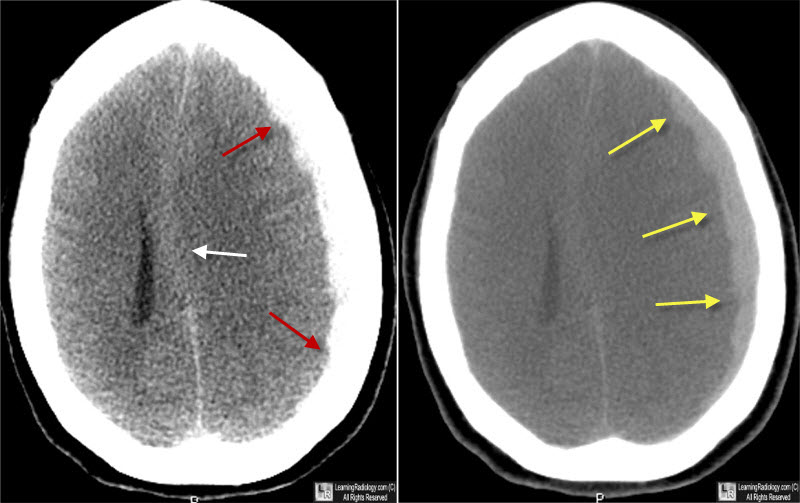

Encontramos una variación sustancial entre centros en el empleo de la craniectomía descompresiva (CD) versus craneotomía para el hematoma subdural agudo traumático. Esta variación en la estrategia de tratamiento no resultó en un resultado funcional diferente. Estos hallazgos sugieren que la CD primaria debe restringirse a pacientes recuperables en los que no es posible el reemplazo inmediato del colgajo óseo debido a la inflamación cerebral intraoperatoria. eClinicalMedicine, 9 de agosto de 2023.

Ensayo clínico de craniectomía descompresiva en traumatismo craneal

08 septiembre 2016

En pacientes con hipertensión endocraneal post-traumática refractaria, la cirugía redujo la mortalidad pero aumentó las tasas de estado vegetativo y de discapacidad severa. New England Journal of Medicine, 7 de septiembre de 2016